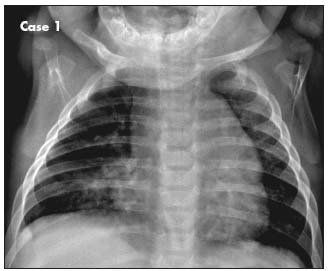

A 6-month-old boy with 1-week history of dry cough that worsened at night. He had been wheezing off and on for the past month and had visited the emergency department on one occasion.